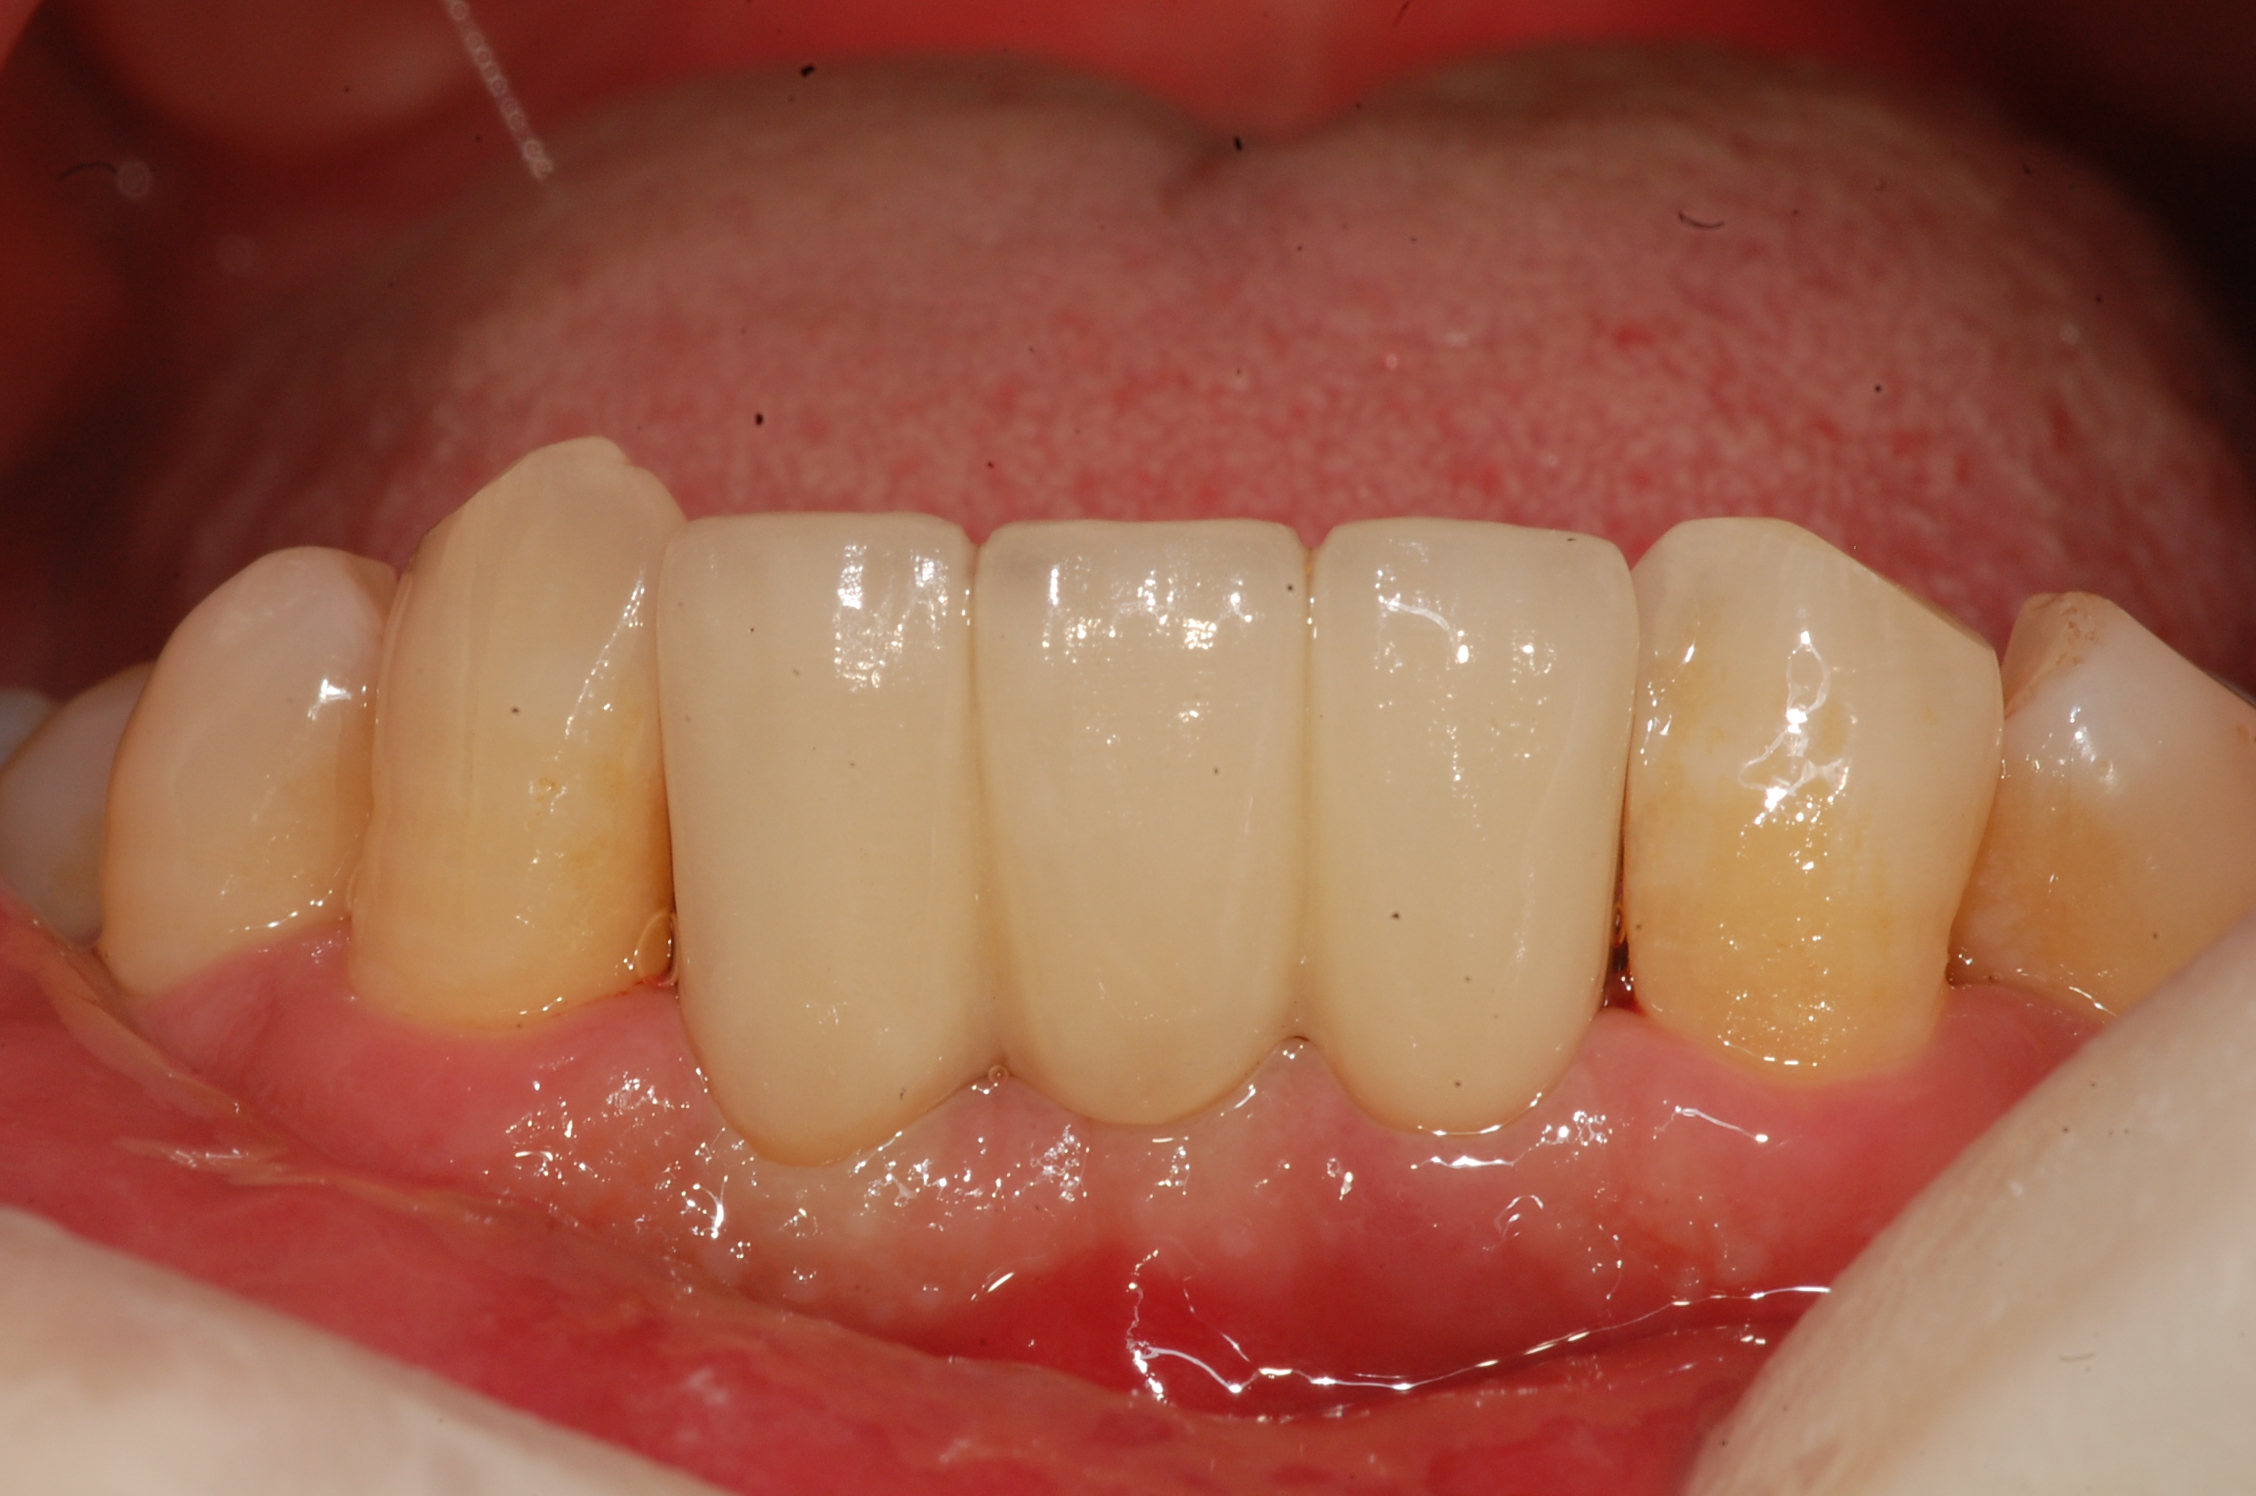

[임플란트] 제목 : 아래 앞니 임플란트

치주질환으로 발치 후 치료